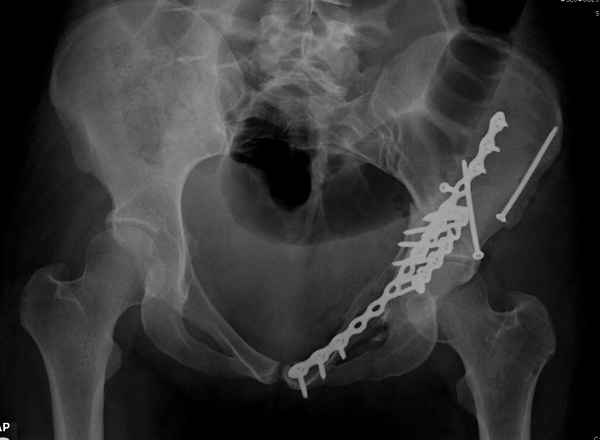

итак, второй вариант: высокий двухколонный с вовлечением КПС... Ни одно из основных повреждений не репонировано, кроме задней стенки. Скорее всего попытка реконструкции вертлуги сейчас будет очень травматичной и не очень эфективной, т.е. вероятный риск более значим, чем ожидаемая польза... Лучше подождать, и потом сразу эндопротез

>Лучше подождать, и потом сразу эндопротез

подождать сколько, чего? такая дыра в задней колонне не закроется никогда.

потом эндопротез какой? в такой ситуации приходит на ум Burch-Schneider cage, в 35 лет, дальше что делать?

Когда перелом не получается отнести к какому либо типу - эффективнее всего описать более детально. В дальнейшем проще бывает сортировать, и что важнее - "руководство к действию" бывает более обоснованным. В данном случае графа клинического диагноза может выглядеть так: Застарелый разрыв правого крестцово-подвздошного сочленения, консолидирующиеся со смещением переломы крыла и тела правой подвздошной кости, обеих колонн и задней гемисферы правой вертлужной впадины. Состояние после остеосинтеза.

Исходя из возраста пациента без сомнения желательно подготовить основу для установки "Press Fit" (Magnum). Одним словом сначала необходимо выполнить Реконструкцию.

>Застарелый разрыв правого крестцово-подвздошного сочленения, консолидирующиеся со смещением переломы крыла и тела правой подвздошной кости, обеих колонн и задней гемисферы правой вертлужной впадины. Состояние после остеосинтеза.

исходя из непонимания паттерна повреждения, как вы собираетесь подготовить впадину? Доступы? сразу протез или реконструкцию или создание bone stock? secondary congruency?

А что Ввам не понятно? И что Вам дадут нового в понимании паттерна данного повреждения "стандартные проекции"? Согласен! Есть детали, которые требуют осмотра пациента, но это детали. А тактика, как уже и говорилось: Реконструкция, потом эндопротезирование. Доступ... Впрочем, нагляднее посмотреть презентацию (прикрепленный файл). В представленном случае все делалось одномоментно - реконструкция и эндопротезирование. Доступы сочетались (задний и подвздошно-паховый). В данном же случае желательно выполнить в 2 этапа.

понимание Классификации Летурнеля позволило бы вам скорее всего выполнить реконструкцию под эндопротез из одного стандартного доступа в одну сессию, а не из двух с непонятным отпиливанием крыльев. Два доступа имели бы смысл, если бы планировалась полная реконструкция сустава в расчете на его функционирование его какое-то время. Представленный вами случай задает больше вопросов, чем ответов. Стоило затевать такую реконструкцию, чтоб установить обычную цементную чашку. Зачем 2 этапа для первичного эндопротезирования?

Из какого одного "стандартного" доступа вы собираетесь выполнить реконструкцию спустя 3 месяца? Из расширенного подвздошно-бедренного или У-образного с flip остеотомией большого вертела. В обеих случаях, скорее всего, разрез будет в проекции послеоперационного рубца. А мы даже пациента не видели. А задние отделы?!!! Надо фиксировать или нет? А если надо, то как, каким доступом? У "непонятного" отпиливания крыла - есть вполне понятные причины и обоснование. Это не ново! Или перкутанно фиксировать КПС? (спустя 3 месяца)!

А почему в 2 этапа? Исключительно для установки press-fit, а не обычную цементную чашку в реконструированную первым этапом и сросшуюся вертлужную впадину.

По-моему, надо готовить больного к будущей артропластике, но без опоры на задний столб невозможно удержать протез. Опорная конструкция (кольца и т.д.) должны иметь опору, и поэтому мы бы сделали реостеосинтез задним доступом. При надобности остеотомия и рутинная фиксация с межколонными винтами.